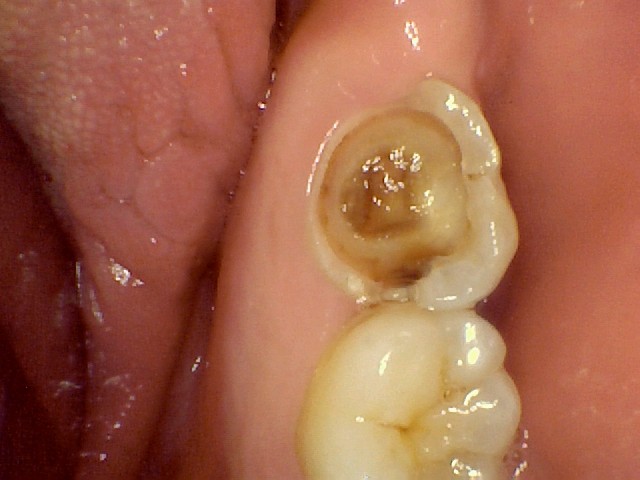

Cavity, prep and restoration